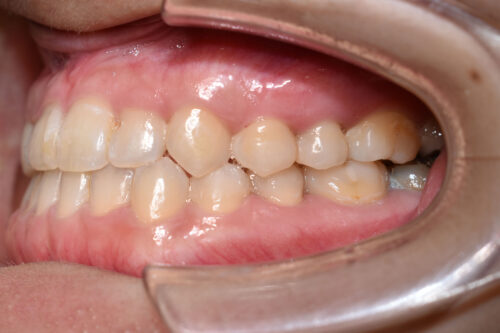

ワイヤー8か月後です。

本症例のように

歯科矯正用アンカースクリュー(デュアル・トップオートスクリュー)を利用し

下顎の後方移動を行うことで

歯を抜かない非抜歯矯正治療でも

受け口を整えることができます。